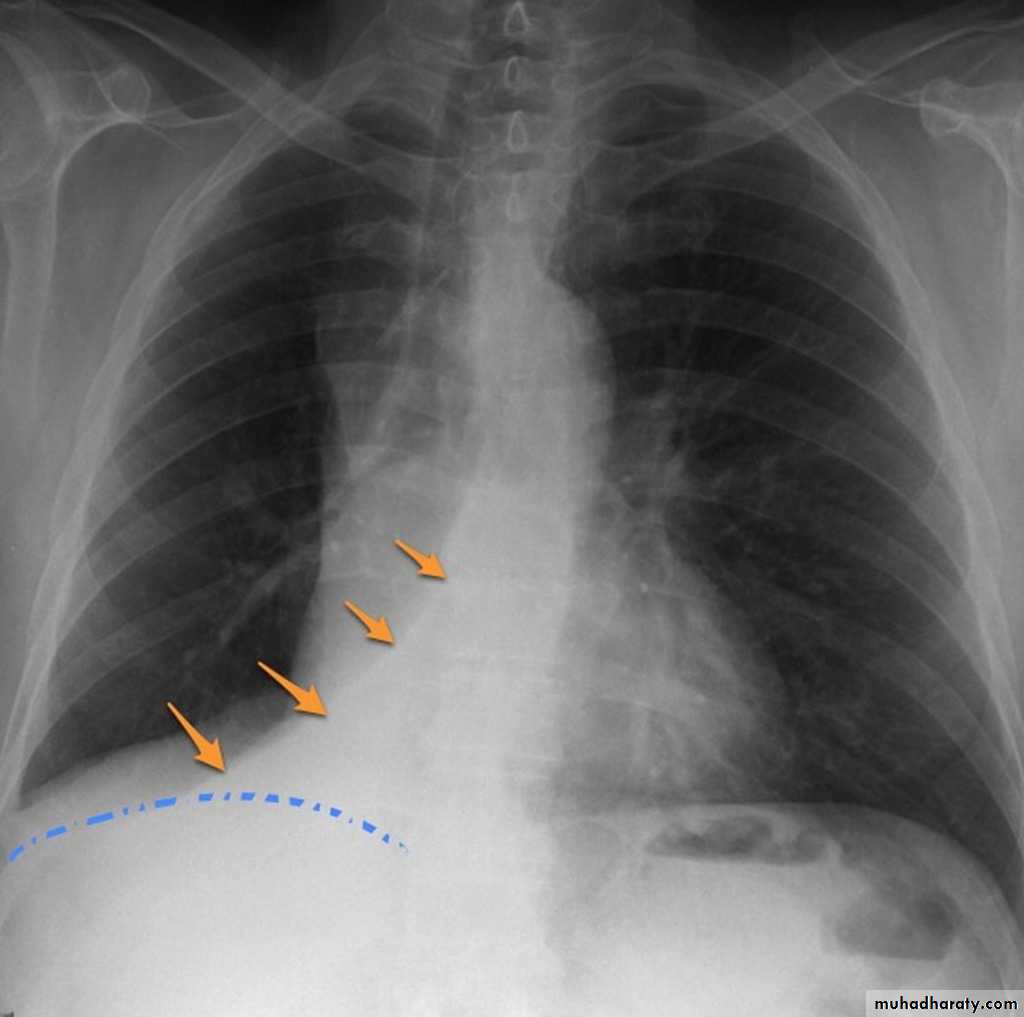

Right lower lobe consolidation

manifests as airspace shadowing that abuts the right hemidiaphragm,

obliterating the crisp margin of the hemidiaphragm and normal aerated lung.

bulging fissure sign refers to lobar consolidation where the affected portion of the lung is expanded. It is now rarely seen due to the widespread use of antibiotics.

The most common infective causative agents are :

Klebsiella pneumoniae

RT lower lobe collapse

usually the medial aspect of the dome of right hemidiaphragm is lost.

the right hilum is depressed

It is important to note that the right heart border, which is contacted by the right middle lobe remains well seen.